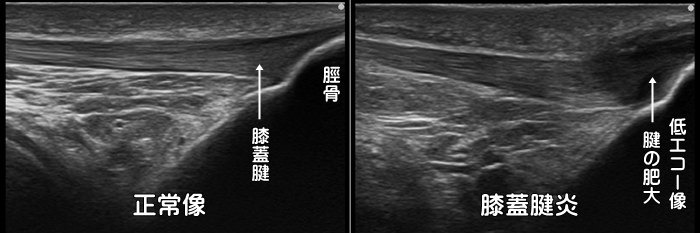

膝蓋腱炎・ジャンパー膝

膝蓋腱炎・膝蓋靭帯炎はバレーボールなどのジャンプ動作で発症するため別名ジャンパー膝とも呼ばれます。トレイルランナーが転倒し膝を強打した際にも好発します。重症化すると膝蓋骨や脛骨付着部の低エコー像(断裂)や腱の肥厚、また炎症による血管増生が見られます。